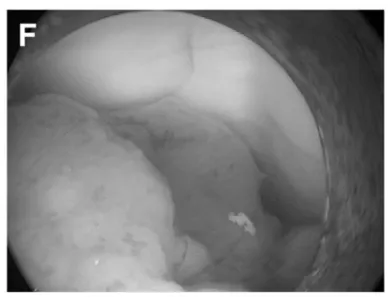

(F)第三脑室后部肿瘤。